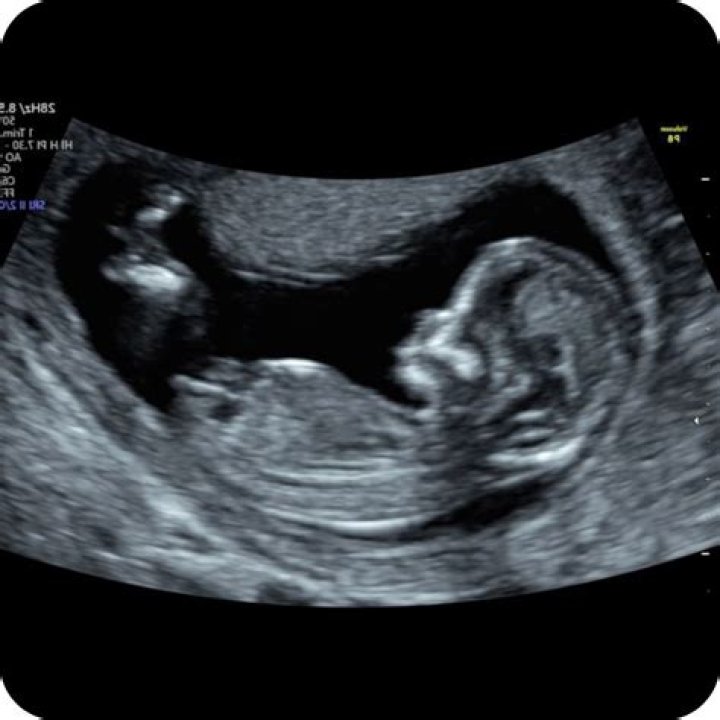

How big is a 12 week scan

At 12 weeks, the foetus is now about the size of a passion fruit, measuring close to 5.5 cm, crown to rump, and weighing approximately 18 grams.

Basic anatomy is visible on the 12-14 week ultrasound. Your medical provider can see if the heart has four chambers; if the brain has two hemispheres; and if the baby has eyes, limbs, lungs, a spine and a bladder, said Dr.

The 12-week ultrasound is usually an external scan. (In occasional cases, an internal — known as transvaginal — scan may be necessary if the external scan can’t produce a clear image.) You’ll lie back on the exam table, and an ultrasound technician will apply a clear gel across your lower belly.

Why is 12 weeks considered safe?

“For the most part, the 12-week rule exists because most woman have an ultrasound scan at 12 weeks,” she says. “That’s really become the benchmark for women to feel like the pregnancy is real.” Dr Nash says historically, the 12-week ultrasound either did not exist or was not standard practice during pregnancy.

The 12-week ultrasound allows your healthcare provider to check how your baby is developing and screen for conditions like Down syndrome. Your practitioner can also determine your due date and how many babies you are carrying with this scan.